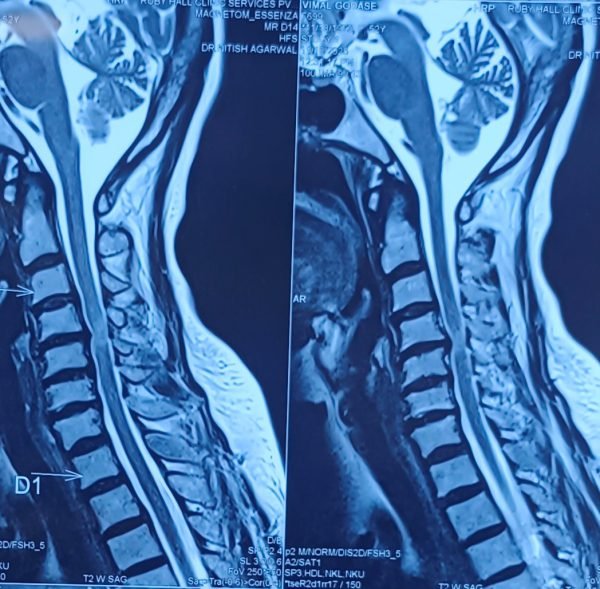

Trustindex verifies that the original source of the review is Google. I visited Dr. Nitish Agarwal for my severe back pain and shoulder issue. He checked my MRI very carefully and gave the perfect diagnosis. Yesterday, he performed the procedure (Root Block and Shoulder Injection), and it was completely painless. He is an expert and targeted the exact nerve point causing the trouble. Very helpful and humble doctor. Highly recommended for anyone with spine problems.Posted onTrustindex verifies that the original source of the review is Google. I was unable to make movement and suffered from right foot drop which is equal to halfway paralysis. Dr. Nitish Agarwal performed very fine microscopic surgery on L3, L4 & L5. After 90 days under his treatment I could go for a walk min. 6 kms a day, I have started my regular activities after 120 days. Thank you so much Dr. Nitish Agarwal sir.Posted onTrustindex verifies that the original source of the review is Google. I was suffering from severe back pain, and Dr. Nitish Agrawal has been extremely supportive throughout my treatment. He listened carefully, explained everything clearly, and guided me very well. His treatment has really helped me recover. He is one of the best spine specialists — highly recommended!Posted onTrustindex verifies that the original source of the review is Google. I had consulted many doctors before Dr Nitish for my mother's spine issue,most recommended complex procedures and surgeries. Fortunately we found Dr Nitish and it has been life changing for my mother,she was in immense pain before the simple surgery he did. It's rare to find a surgeon who explains everything in detail and provides such exceptional care even after the surgery. I Would highly recommend him.Posted onTrustindex verifies that the original source of the review is Google. My mother had sustained a fracture to her right hand wrist and we were worried about her recovery due to age factor. One of our family Doctor referred us to Dr. Nitish Agrawal and we visited Dr. Nitish Sir. Dr. Nitish sir ensured that my mother don't need a surgery and treated her by application of plaster (temporary and then cast-iron or Firm plaster) with certain orthopaedic treatment to hand and prescribed oral medication for ensuring recovery is faster without any surgery. Attaching the photo of xray which shows recovery of wrist bone which has rejoined and we are still continuing treatment to ensure my mother is fully recovered and is fit. Thank you Dr.Nitish Agrawal for your support.Posted onTrustindex verifies that the original source of the review is Google. Hi everyone, myself Samadhan. I was suffering from severe spine pain for a long time, and one of my friends suggested I visit Dr. Nitish Agarwal. Honestly, that was the best advice! Dr. Nitish listened to my problem very patiently, explained the cause in detail, and gave me the right treatment. I started feeling better within a short time. He is very polite, knowledgeable, and truly cares for his patients. I highly recommend Dr. Nitish Agarwal for anyone dealing with spine or back pain. Thank you, doctor, for your excellent treatment and support!Posted onTrustindex verifies that the original source of the review is Google. Dr. Nitish Agrawal is an excellent spine specialist who patiently listens, explains the problem clearly, and provides the best treatment options.Posted onTrustindex verifies that the original source of the review is Google. Dr.Nitish sir is an incredible surgeon. I had excellent results from my recent spine surgery. The entire process, from consultation to recovery, was handled with professionalism and care. The outcome has been life-changing. I highly recommend Dr.Nitish agarwal to anyone in need of a spine surgeon.Posted onTrustindex verifies that the original source of the review is Google. A few months back I took treatment for my back pain from dr. Agarwal sir ...last 7-8 years i was suffering with low back pain,unbale to stand for more than 10 minutes..My low back hurts continuously, and also left leg pain was unbearable....i try every possible way of treatment from various suggestion...After several treatment...one of my relative suggested dr. Nitish Agarwal sirs name then I visited Dr. Nitish Agarwal sir in clinic. He suggested me x ray and MRI. On that basis he advise me caudal Block with root block with facet block for pain management. After block my pain goes with in a week. He advise me regular Physiotherapy at home. Now after regular exercise I am pain Free. Dr. Nitish Agarwal is a good doctor for any spine related problem.... Thank u dr. Agarwal Sir 🙏Posted onTrustindex verifies that the original source of the review is Google. My wife had major infection in neck and lower back. She was bedridden. her legs and hands were weak. Then we admit her under Dr. Nitish Agarwal sir and did MRI. He explained that she is having major infection in cervical and lumbar spine. Due to infection her spinal cord is compressed so she was not able to walk. Then sir did operation for neck and removed infected tissue and spinal cord is freed and put a plate. Her lower back is treated with medicine only. She was given 2 months antibiotics by saline and 5 months oral antibiotics were given. He also advised regular exercise. After 15 days of surgery she started walking with support. Now after 1 year she is completely alright and walking like a normal person. She is regularly doing all her activities. Now she can also travel by 2 wheeler. Thank you to Dr. Nitish Agarwal sir for his expert work in spine. I recommend Dr. Nitish Agarwal for any spine related problem.